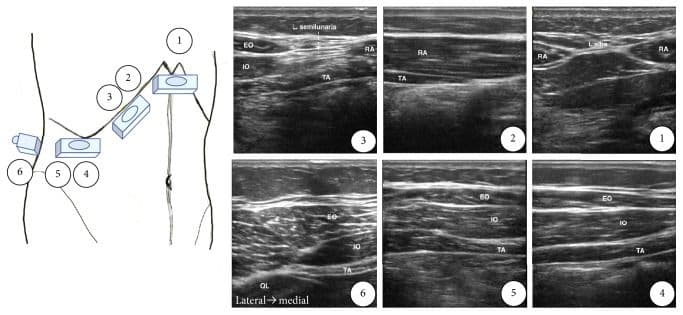

Субкостальний ТАР-блок

Лінійний датчик розміщують вздовж нижнього краю грудної клітки якомога медіальніше та краніальніше. M. rectus abdomini та його задня сполучнотканинна піхва візуалізуються разом з m. transversus abdominis [5,6,13,25].

Цільовою є фасціальна площина між задньою сполучнотканинною піхвою m. rectus abdominis та m. transversus abdominis. Голку вводять вище прямого м'яза живота близько до середньої лінії та просувають у латеральному напрямку. Ціллю ін'єкції є поширення місцевого анестетика між задньою сполучнотканниною піхвою прямого м'яза живота та переднім краєм поперечного м'яза живота [5,6,13,25].

Середньоаксилярний ТАР-блок

Для виконання цієї блокади лінійний датчик розміщують в аксіальній площині по середній пахвовій лінії між краєм реберної дуги та гребенем клубової кістки. Візуалізують три шари м'язів стінки: зовнішній та внутрішній косі м'язи живота, а також поперечний м'яз живота. Ціллю є фасціальна площина між внутрішнім косим м'язом живота та поперечним м'язом живота. Голку вводять по передній пахвовій лінії, і кінчик голки просувають до досягнення фасціальної площини між внутрішнім косим м'язом живота та поперечним м'язом живота приблизно по середній пахвовій лінії [5,6,13,25].